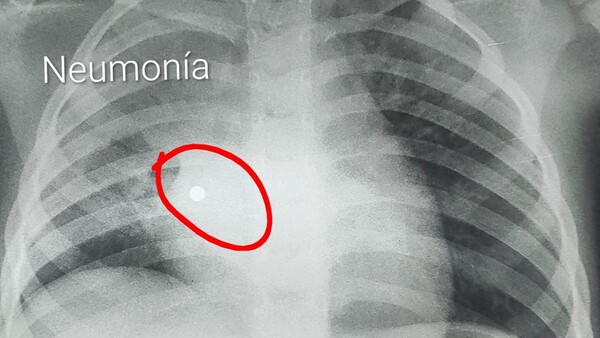

Nena de 4 años tragó cinco perlas y acabó en terapia intensiva

Cuatro de las pelotitas de un collar fueron al aparato digestivo, pero una fue a parar en el pulmón y causó una grave infección. ...[Leer más]